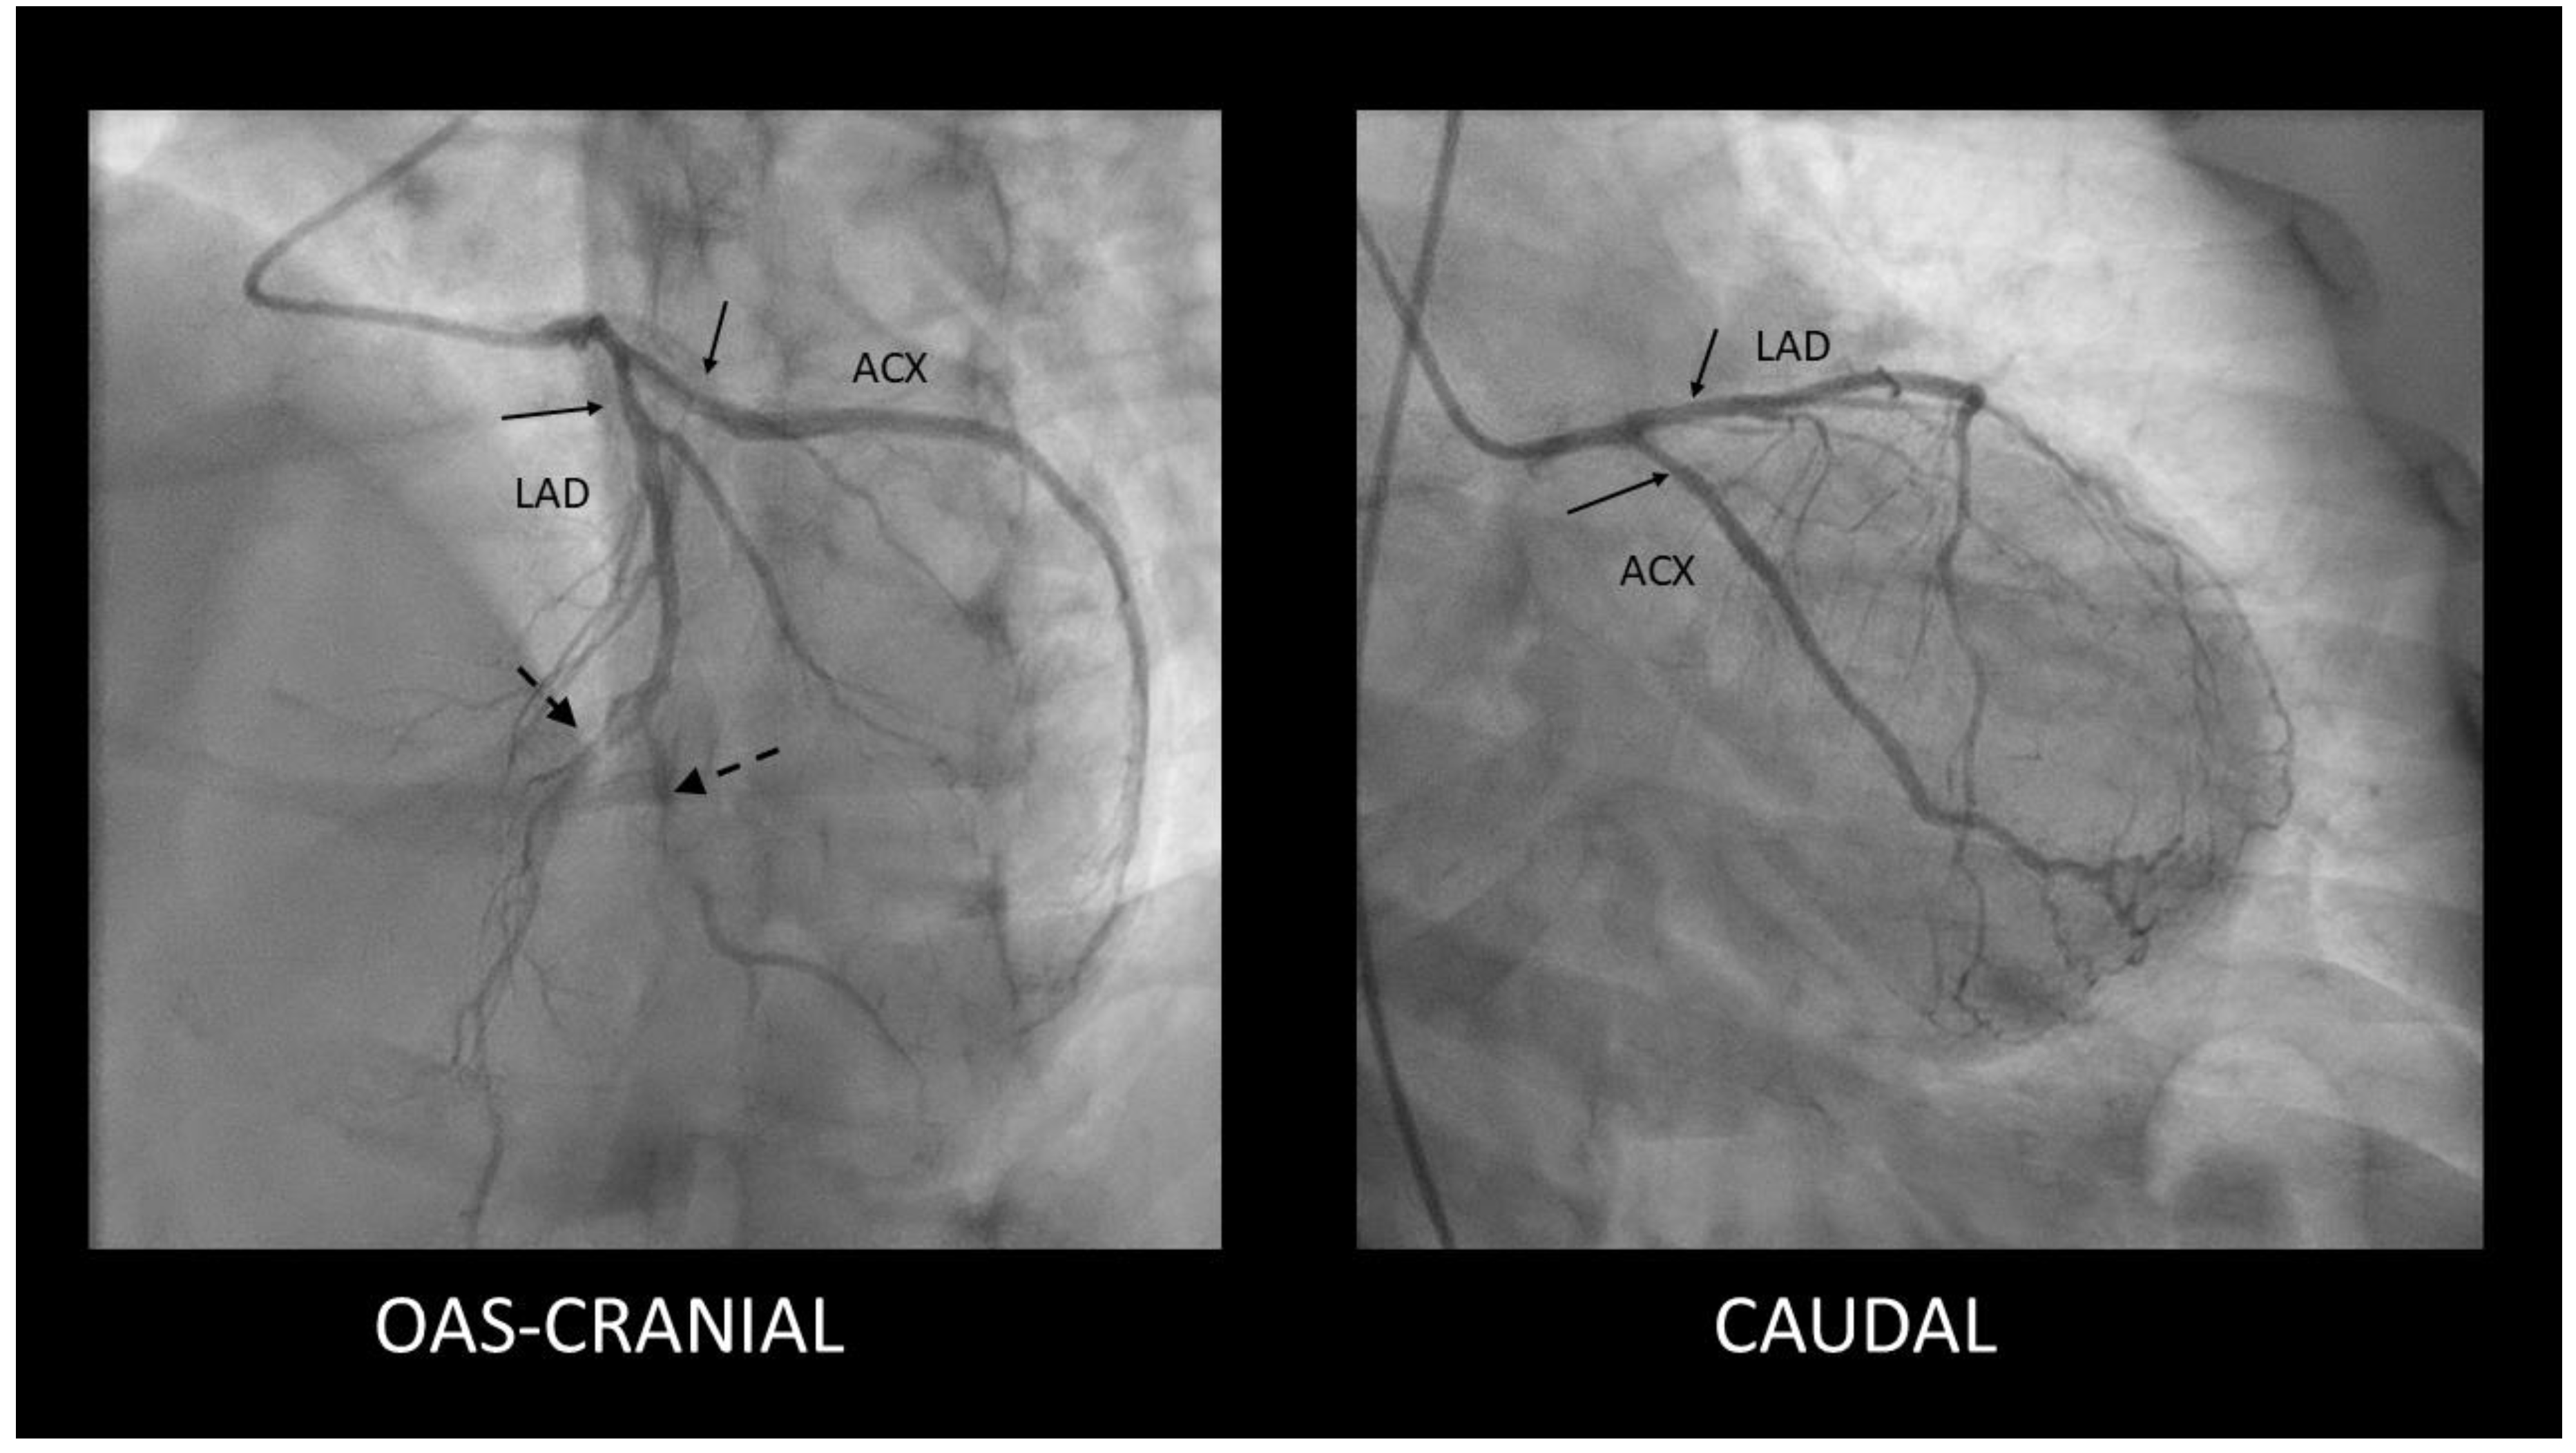

- SCAD type 2- long, diffuse, usually tubular lesion, longer than 20-30 mm, without a visible intimal flap or double lumen. The type 2 lesion does not ameliorate after intracoronary nitroglycerine administration (in contrast with coronary spasm). This type is the most common angiography pattern, being present in over half of SCAD cases (60-70%) [5,31,33] (Figure 2).